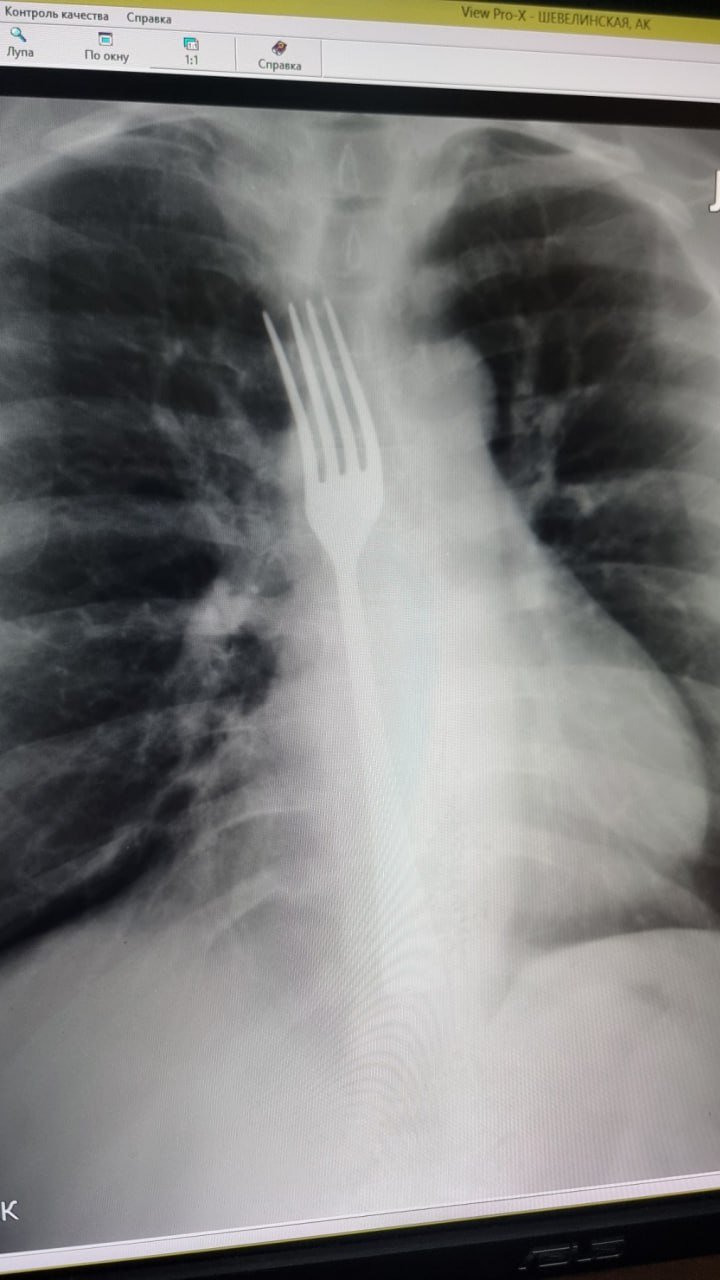

Инцидент произошел в Витебске. Женщина столкнулась с проблемой – «встал желудок». Не найдя ничего лучше, витебчанка попыталась вызвать рвоту вилкой. Пара неловких движений – и прибор застрял у нее в пищеводе. Срочно вызвали скорую и женщину доставили в областную больницу прямиком на операционный стол. Белоруске сделали «зонд» под наркозом и частично опустили вилку в желудок. Затем разрезали живот и извлекли инородный предмет. 1